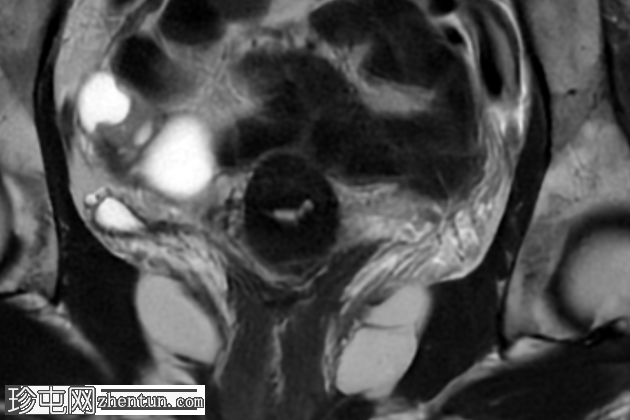

轴位T1加权像

脂肪抑制像

盆腔MRI显示右侧卵巢解剖位置可见一边界清晰的卵圆形肿块。该病灶由囊性和实性成分组成。囊性部分壁薄,在T2加权像上呈均匀高信号,在T1加权脂肪抑制序列上呈低信号,无对比剂增强。该实性成分的信号特征与正常卵巢组织相似,DWI成像未见扩散受限,静脉注射造影剂后未见异常强化。

此外,在子宫左侧壁可见一管状薄壁囊性结构,延伸至同侧髂外血管,末端呈盲端。该结构在T2加权像上呈均匀高信号,在T1加权脂肪抑制序列上呈低信号,且无造影剂强化。

主要鉴别诊断包括腹膜包涵囊肿、子宫内膜异位症相关囊肿和附件肿瘤。腹膜包涵囊肿通常位于腹膜腔内,不含类似卵巢组织的实性成分。子宫内膜异位囊肿通常在T1加权像上表现为高信号,T2加权像上出现阴影,并具有其他特征性MRI表现,而本例4中均未见这些表现。鉴于无扩散受限、无可疑强化以及实性成分的良性影像学表现,肿瘤性病变的可能性较小。